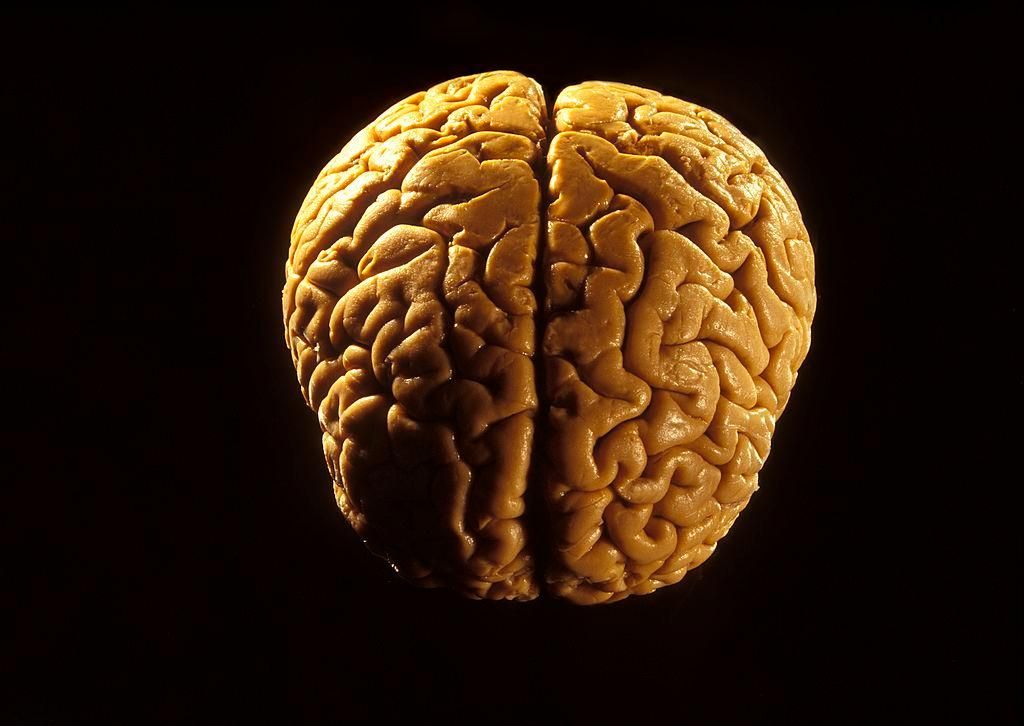

Il cervello è l’organo più complesso e meraviglioso del nostro corpo. Tuttavia, è una struttura misteriosa ed è avvolta da numerosi equivoci e bufale.